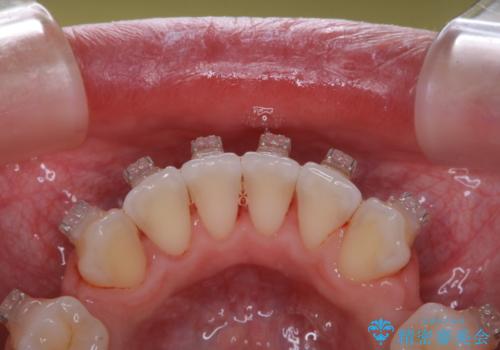

20代女性 ワイヤー矯正中にワイヤーを外してきれいにクリーニンング

- 審美装置でのワイヤー矯正中の方です。月に1度の調整の際に一緒にクリーニンングもしてほしいとのことでした。

ワイヤーを上下外して、PMTC60分コースを行いました。

ワイヤー矯正中はブラッシングが難しくなるため、磨き残しが多くなることがあります。